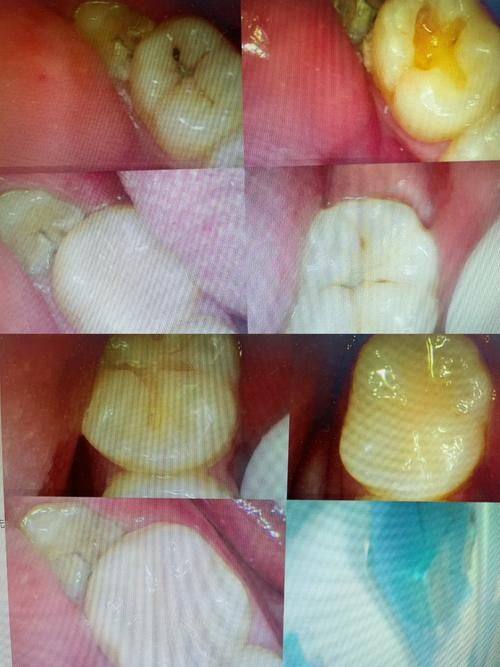

美学修复:提供爱尔创、威兰德、泽康、lava等品牌牙冠修复服务,结合数字化技术定制个性化修复方案,修复后牙齿形态自然、色泽逼真,能有效改善牙齿外观。

儿童齿科:接诊3-12岁儿童,开展儿童龋病治疗、早期颌面发育干预等项目,医护人员对儿童患者耐心细致,诊疗环境童趣化,降低儿童看牙的抵触情绪。